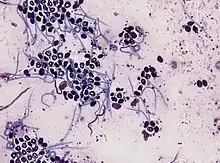

Onchocerca f

- A taxonomic genus within the family Onchocercidae – parasitic roundworms that cause river blindness.